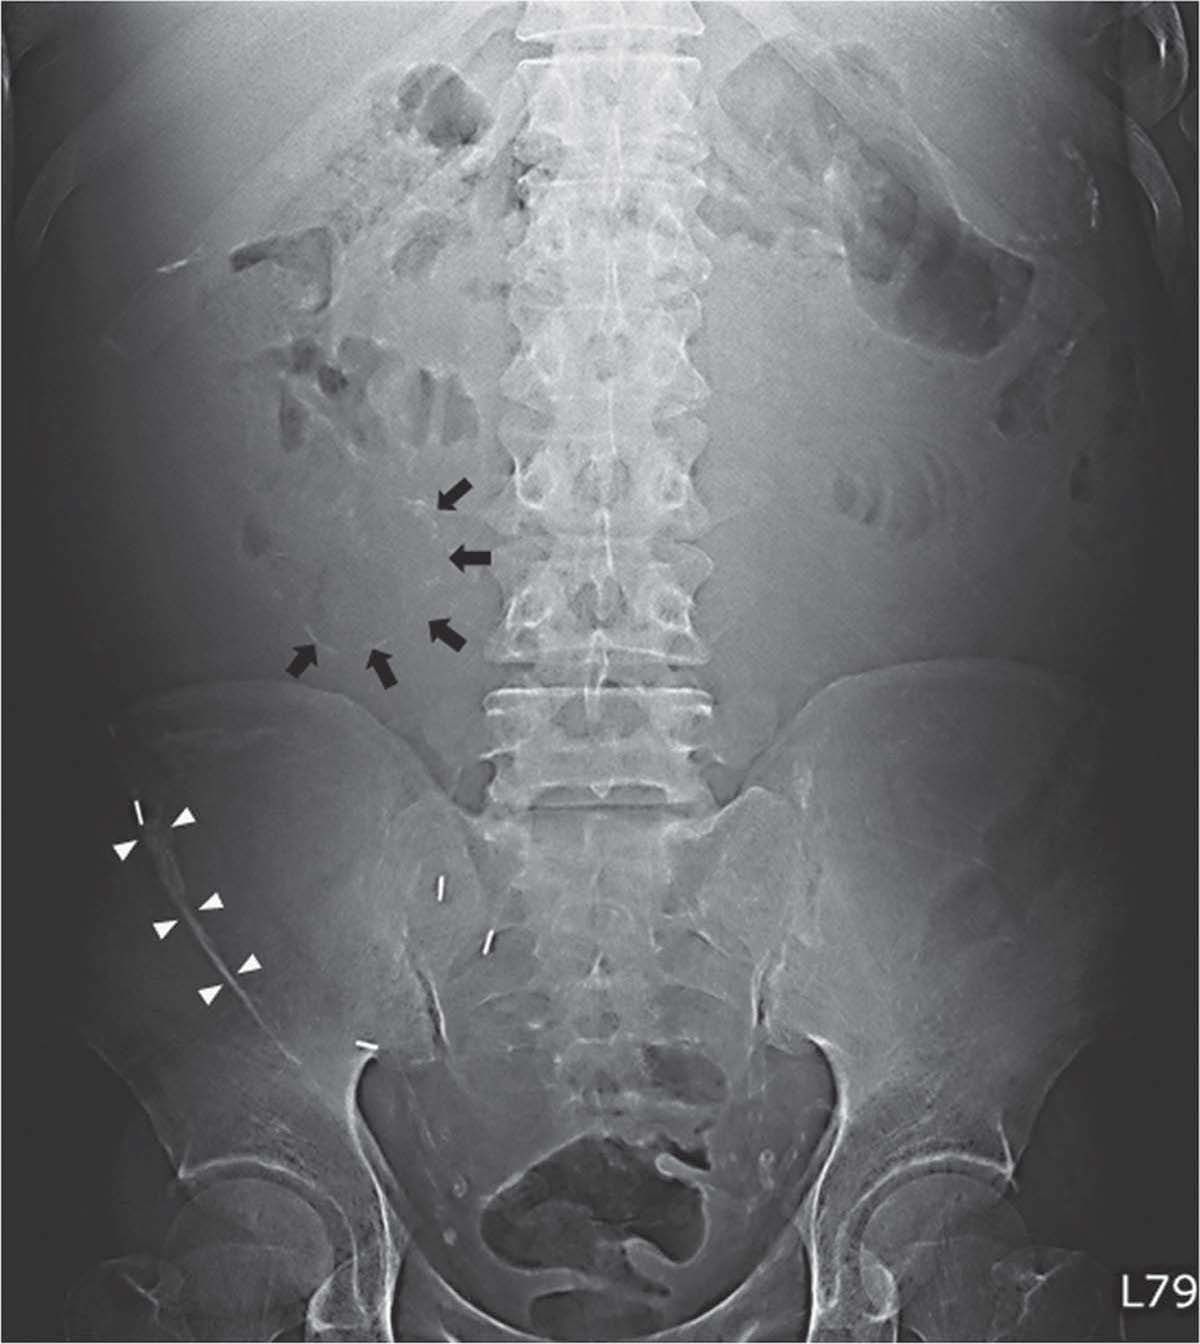

revealed normal blood leukocyte count (WBC: 7,100/mm3 ) but an elevated C-reactive protein level (50.3 mg/l). An abdominal radiograph was obtained to evaluate his symptoms. The intestinal wall was outlined by continuous calcifications (Figure 1 , arrows), and the curvilinear calcification on the right side of the radiograph was peritoneal calcification (Figure 1, white arrows). A contrast enhanced